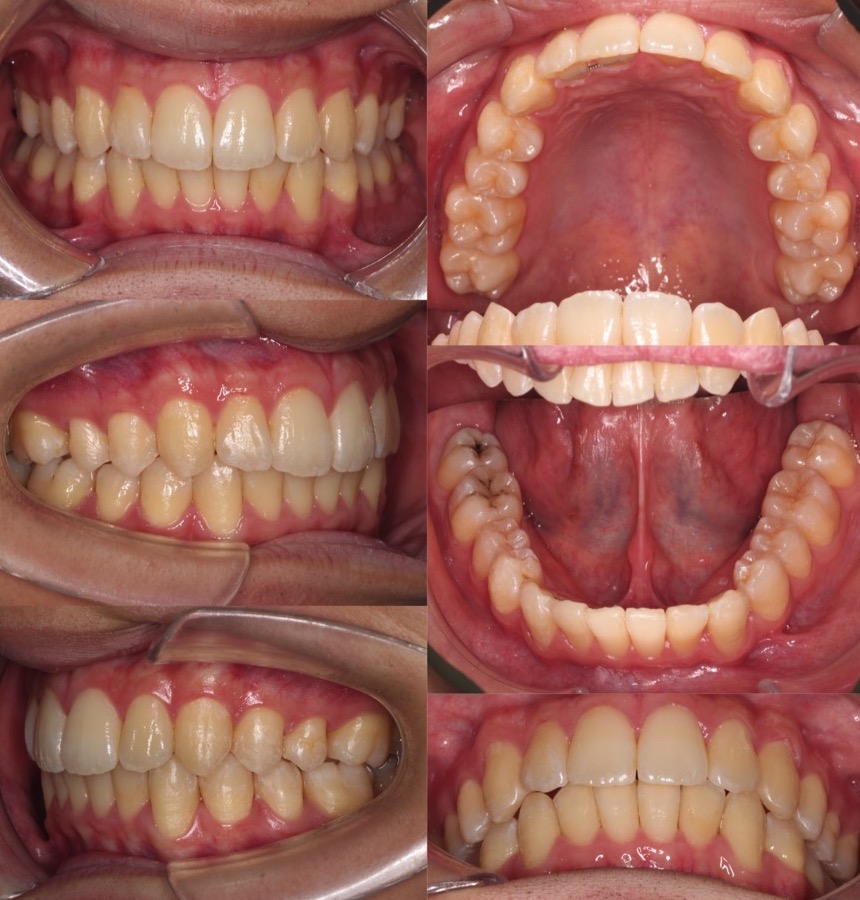

高校生女性・中程度叢生・唇側矯正装置・抜歯

八重歯と上下の正中線の不一致があるケースです。左右の抜歯部位を変えたり、下の歯並びをIPRも併用して顎間ゴムで回転させることで正中線を上下の正中線を一致させました。骨格に大きな非対称がなかったため上手くいったケースになります。

<症例概要> 難易度★★★☆☆

主訴:でこぼこ

年齢・性別:高校生女子

住まい:千葉県八千代市

症状:叢生・正中線不一致

治療方針:抜歯空隙閉鎖・右下後方移動・IPR

抜歯:右上第二小臼歯・左上第一小臼歯

治療装置:唇側矯正装置

治療期間:1年11か月

リテーナー:上下プレートタイプ+フィックスタイプ

治療費用:968,000(税込)

代表的副作用:痛み・治療後の後戻り・歯根吸収・歯髄壊死・歯肉退縮